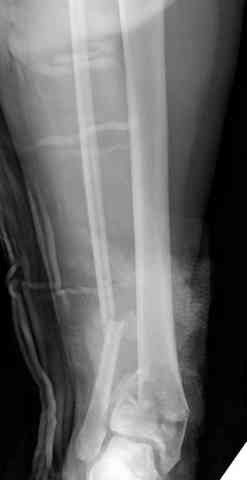

Добавлены КТ снимки. Прошу прощения за качество.

С уважением, Коваленко А.Н.

Снова приветствую вас, коллеги. К моменту вступления в обсуждение аксакалов, операция была, увы, выполнена(31.10.07.) Начали с доступа к наружной лодыжке, произвели ее фиксацию спицами, развернули кусок заднего края, наложили дистрактор, затем произвели дистракцию, фиксацию спицами дистального эпиметафиза б/бк,Рентгено-контроль. синтез наружной лодыжки 1/3пластиной. из двух коротких разрезов сформирован канал под медиальную тибиальную пластину LCP. Края ран ушиты без натяжения. Прочувствовать жесткость фиксации винтами с угловой стабильностью не удалось, поэтому дистрактор оставлен на энное время.

На представленных R-снимках не окончательный вид после остеосинтеза. Дистальная опора давила на стопу, пришлось ее сместить проксимально, в рез-те чего, она закрыла щель сустава, последние снимки не информативны.